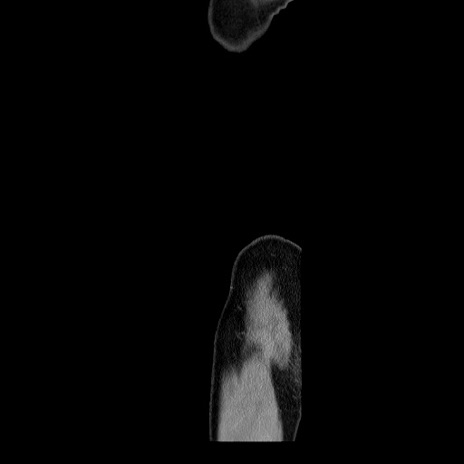

横断像